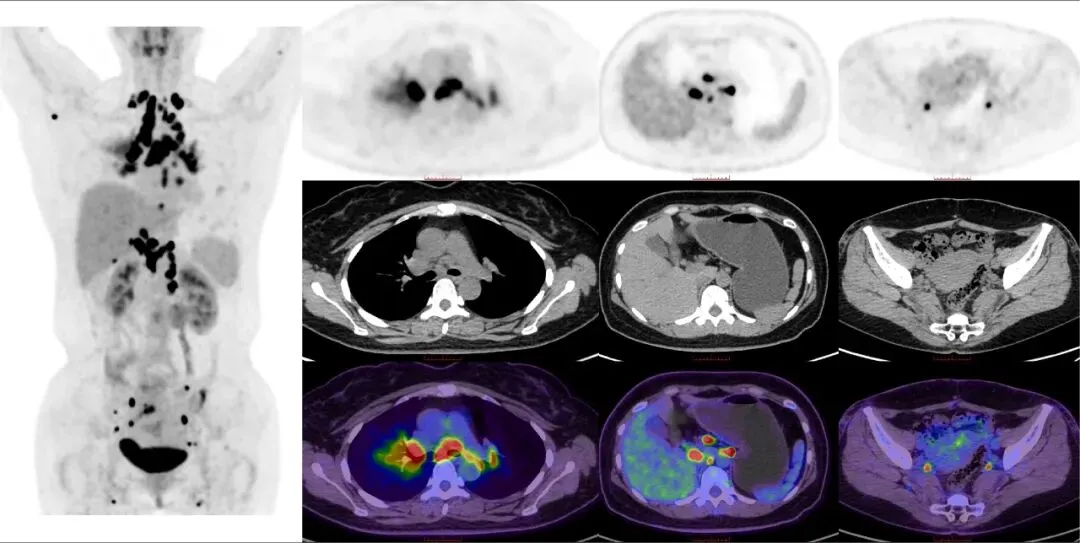

CASE 2

女,35岁,发现腹膜后肿物2天。患者因腹部不适就诊于外院,腹部CT提示腹膜后腹主动脉旁结节、肿块,考虑为肿大淋巴结可能。我院18F-FDG PET/CT示双侧锁骨上窝、右腋窝、双肺门及纵隔、肝门、腹膜后、髂血管旁、盆壁、腹股沟区多发淋巴结,部分肿大,糖代谢异常增高;双肺条片状稍高密度,糖代谢增高。